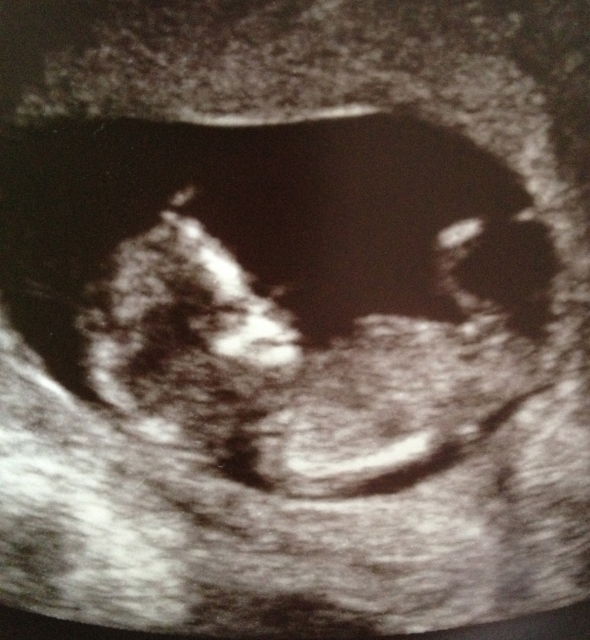

If anyone take a guess at my 12 week scan?

I think I see a nub right below the leg bone and it looks girl to me.

I was going to say girl, too, but I see your signature say's it's a boy. How do you know for sure? And what was the gestation in this pic?

At 16+5 weeks the tech said boy, I am not 100% convinced it was cause I only saw the nub no scrotum. All my others were very obvious, this one wasn't. Will find out in 10 days.

I don't see any obvious clues here. So, slight girl lean cuz you would think a boy might be more obvious by 16 weeks.

Well we did have another scan and there was no mistaking it. At 17 weeks we just saw a nub, but at 20 weeks we saw the penis and scrotum. So yeah a boy all the way!!